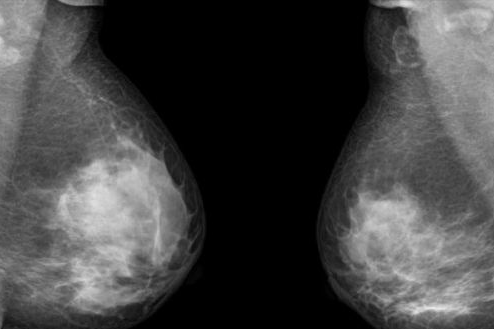

双乳房切除术人数10年涨3倍 乳腺癌患者生存率几无变化

美国过去10年来实施双乳房切除术的女性人数增长了3倍,但科学家们表示目前尚无法确定双乳房切除术是否可以增加乳腺癌患者的生存几率。

据合众社报道,虽然许多女性乳腺癌患者选择实施了双乳切除术来降低乳腺癌的复发风险,但目前的数据人无法确定该预防手术可以挽回乳腺癌患者的生命。

科学家们对1998至2-12年间被诊断为患有乳腺癌的496488人进行了调查研究,其中59.6%的患者选择了保乳手术,33.4%的患者选择了单侧乳房切除术,7%的患者选择了预防性双乳切除术。女性选择双乳切除术的比例从2002年的3.9%上升到了2012年的12.7%。